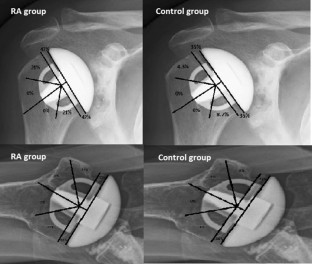

Fig. 1

Fig. 2

Fig. 3

Fig. 4

Fig. 5

Fig. 6